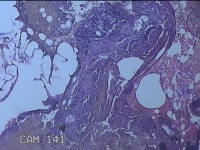

外阴部包块

性别

女

年龄

28岁

临床诊断

1.疖肿病 2.皮脂腺囊肿

一般病史

外阴部起丘疹疼痛一周。

标本名称

大体所见

灰白暗红色包块1x0.7x0.3cm一个,表面糜烂。